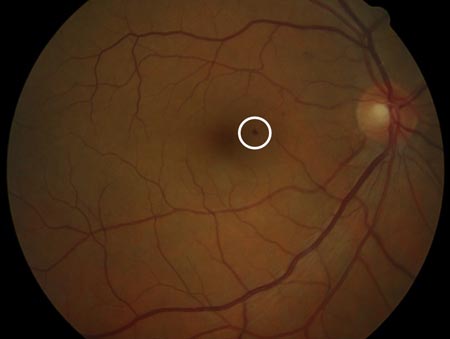

Non-proliferative diabetic retinopathy: blot haemorrhage (white circle)

Courtesy of Moorfields Photographic Archive; used with permission